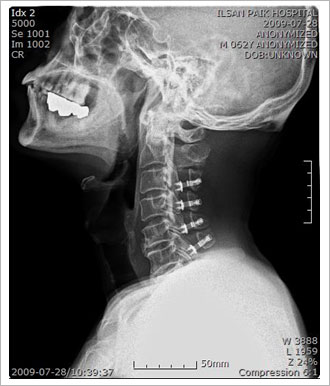

Àü¹æ°ú ÈĹæ Á¢±Ù¹ýÀ» µ¿½Ã¿¡ ÇÏ´Â ¹æ¹ý

ô¼öÁõ°ú Èĸ¸°î, °æÃßÀÇ ºñÁ¤»óÀûÀÎ Ä¿ºê(curve)°¡ ÇÔ²² ÀÖ´Â °æ¿ì°¡ ÀÖÀ¸¸ç Ä¿ºê°¡

À¯¿¬¼ºÀÌ ¾ø´Â °æ¿ì¿¡´Â µ¿½Ã¿¡ ÇØ¾ß¸¸ ÇÕ´Ï´Ù.

Ãßü ¾ÆÅ»±¸ ¹× ºÒ¾ÈÁ¤¼ºÀ» µ¿¹ÝÇÑ ½ÉÇÑ Ã´Ãß º¯¼º º¯È¿Í Àü¹æ¿¡¼ÀÇ Ã´¼ö ¾Ð¹ÚÀÌ È²»ö

ÀδëÀÇ ºñÈÄ, ÇÔ¸ô µî ÈÄ¹æ º´¸®¿Í µ¿¹ÝµÇ°Å³ª, ¼±ÃµÀûÀ¸·Î ôÃß°üÀÌ Á¼Àº °æ¿ì¿¡´Â

¾î´À ÇÑ ÂÊÀÇ ¼ö¼ú¸¸À¸·Î´Â ¿ÏÀüÇÑ Ã´¼ö °¨¾ÐÀ» ¾ò±â ¾î·Æ°í ÀüÈÄ¹æ º´Çà ¼ö¼úÀÌ ÇÊ¿äÇÕ´Ï´Ù. |